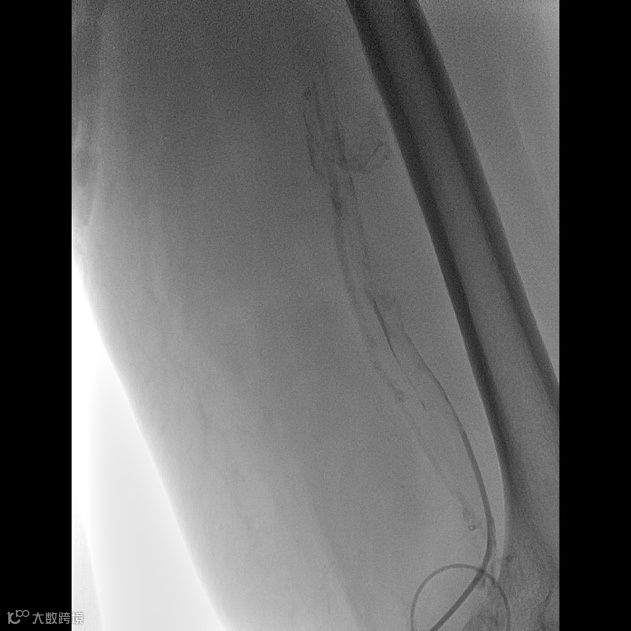

由沈阳市第一人民医院介入科陈建军主任团队运用中天天航™Pro血栓抽吸导管治疗一例急性左下肢深静脉血栓形成且伴有右下肢血流淤滞病变,成功清除血栓并快速恢复肢体灌注,欢迎大家阅读、分享、交流!

手术过程

术后总结